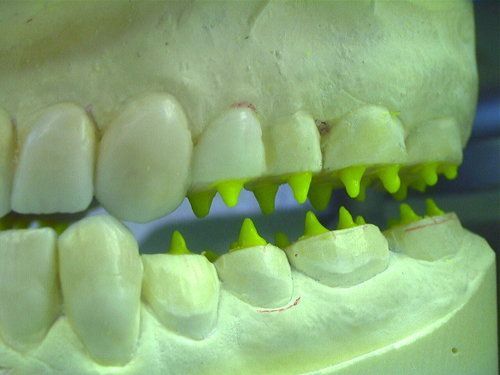

ABSTRACT El Bruxismo es una entidad patológica en la que concurren diferentes factores. Entre ellos el stress que conlleva consigo la vida moderna, constituye el Factor Predisponente sobre el que se ha abundado en innumerables tratamientos de tipo general, actuando sobre la psiquis y el comportamiento del individuo, ya sea con fármacos o bien mediante medios psicológicos. Sin embargo, como tantos desequilibrios provocados por el stress, confluyen siempre con un Factor Desencadenante, que en el caso del Bruxismo se encuentra en las desarmonías entre los componentes varios del Sistema Estomatognático. DESARROLLO Paciente varón, de 43 años, constitución atlética. A la inspección se observan desgastes oclusales que alcanzan la calidad de Facetas Parafuncionales, con dentina expuesta y empastes totalmente gastados y evidentes signos de falta de Disclusión Canina de ambos lados. Sobre dicho montaje se realiza un Encerado Progresivo de Diagnóstico, aportando en el mismo los elementos necesarios para obtener todos los principios básicos de una Oclusión Orgánica. FIG. 6 a 24 Una vez aprobado el fisiologismo de la oclusión en el articulador, se reproducen modelos de yeso con la nueva situación, y se estampa un SET UP en cada maxilar. FIG. 25/26 Procedemos entonces al tallado de las piezas correspondientes a la Guía Anterior, y rebasamos los estampados, creando en boca una nueva situación desoclusiva, que permanece en boca durante los pocos días que transcurren entre la primera y segunda visita de trabajo. FIG. 27/33 Ya abordando en esta segunda visita los sectores posteriores, tanto superiores como inferiores, tallamos siempre de manera supragingival, destacando la importancia vital de la forma obtenida en las provisionales, a las que abrimos plenamente las troneras para lograr una correcta higiene. FIG.34 a 43 FIG. 44 a 52 Efectuados los colados en oro y probados en boca, en el laboratorio se confecciona el bizcochado de la nueva Guía Anterior, la que puede o no copiarse de la Guía Anterior provisional, mediante la técnica denominada Trayectoria Funcionalmente Generada, que consiste en realizar en la platina del articulador un registro estereográfico sobre acrílico Duralay en polimerización. FIG. 57/58 Ajustados todos los detalles mediante esta técnica, se instala en boca en forma Provisional y se deja funcionando una semana o dos, al cabo de las cuales se chequean las disclusiones , los ajustes, la eficacia masticatoria, la carencia de sintomatología articular y muscular. FIG.59 a 63 PIE DE FOTO FIG.9 OBTENCIÓN DE LA GUÍA ANTERIOR FIG.10 Y 11 PITOMBOS. ALINEAC. TRIDIMENSIONAL FIG.12 PITOMBOS. DISCLUSIÓN DER. FIG.13 PITOMBOS. DISCLUSIÓN IZQ. FIG.14 WILSON INF. FIG.15 WILSON SUP. FIG.16 BOCA DE PEZ INF. FIG.17 BOCA DE PEZ SUP. FIG.18 VISTA OCLUSAL FIG.19 O.R.C. FIG.20 DISCLUSIÓN DERECHA FIG.21 CRESTAS TRIANG. INT. FIG.22 CRESTAS TRIANG. INT. FIG.23 CRESTAS TRIANG. INT. FIG 24 CRESTAS TRIANG. INT. FIG.59 DISCLUSIÓN IZQ. FIG.60 DISCLUSION IZQ. FIG.61 DISCLUSIÓN DER. FIG.62 DISCLUSION DER. FIG. 63 AJUSTE PERIFÉRICO